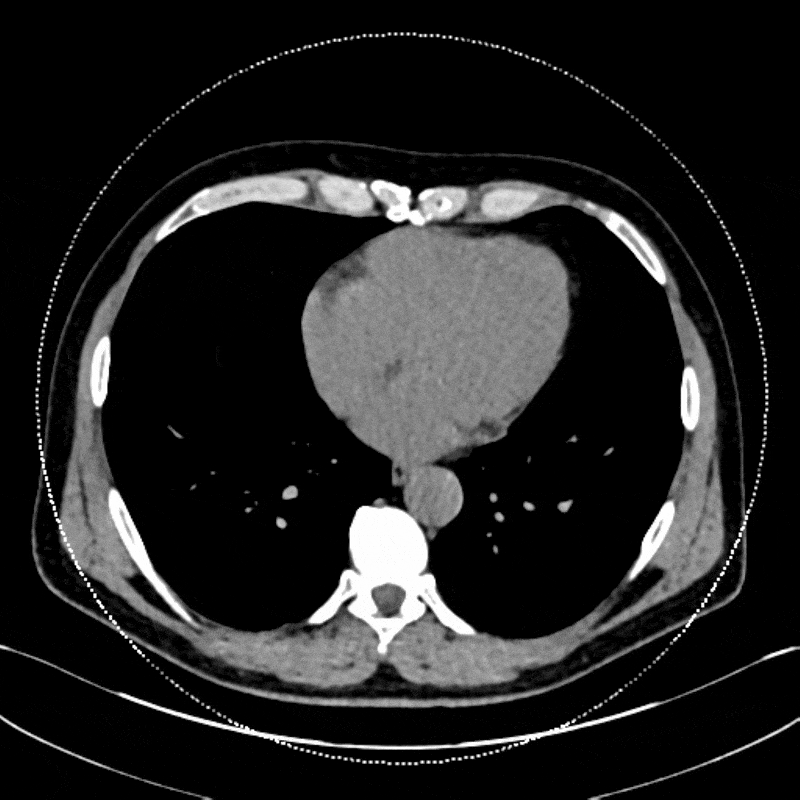

Kidney stones are hard mineral deposits that form in the kidneys and can cause severe pain, bleeding, or infection when they obstruct the urinary tract. Treatment depends heavily on the type of stone, as different compositions respond to different therapies. For example, uric acid stones can often be dissolved with medication, while calcium-based stones typically require physical removal. Standard CT is excellent at detecting stones, but it cannot reliably tell one type from another, leaving clinicians to rely on guesswork or post-removal analysis.

Dual energy CT offers a major improvement by allowing radiologists to identify stone composition non-invasively. By capturing images at two X-ray energy levels, it distinguishes uric acid from calcium and other stone types based on their material-specific attenuation patterns. This helps guide treatment from the start, determining whether a patient may benefit from medical management or needs surgical intervention. It can also reduce the need for repeat imaging or exploratory procedures. For patients with recurrent stones, DECT provides valuable insight into stone behavior over time, supporting more personalized prevention strategies.

Figure D: Axial dual energy CT images of the abdomen, used for analyzing the composition of kidney stones.

Figure E: The axial images of the abdomen from Figure D, now processed to analyze the composition of the kidney stone (indicated by the arrow).

Figure F: Processed images from Figure E, showing graphics that detail the stone’s size, volume, and composition.